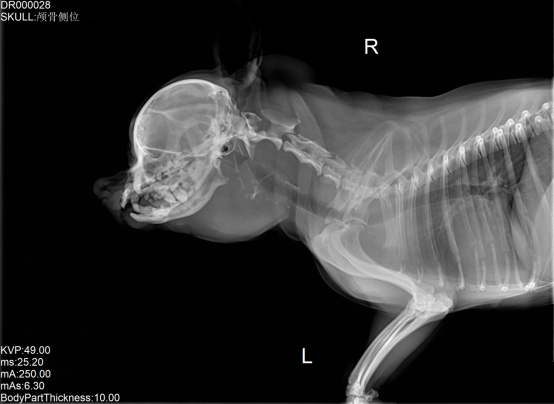

宠物DR是专业用于宠物X光拍摄的数字化X射线检查,辅助宠物医生进行及时精确的诊疗。宠物DR主要包括五大主要部件,数字X光探测器,高压发生器,球管,机架,宠物专用的DR工作站软件。宠物DR由于采用数字技术,自动成像处理,模拟X线图像向数字化X线图像的转变。宠物DR与传统模拟X光机相比有什么优势呢?采集时间10毫秒以下,成像时间仅为3秒,较高的空间分辨力和低噪声率,提高了病灶的检出率,避免漏诊误诊等问题。减少X线对人体照射的不良影响宠物DR照片是您最佳的选择。提高宠物医生工作效率,总而言之,选择宠物DR是宠物医院的最佳选择。宠物医学影像学实现全数字化和无胶片化升级发展提高技术水平。